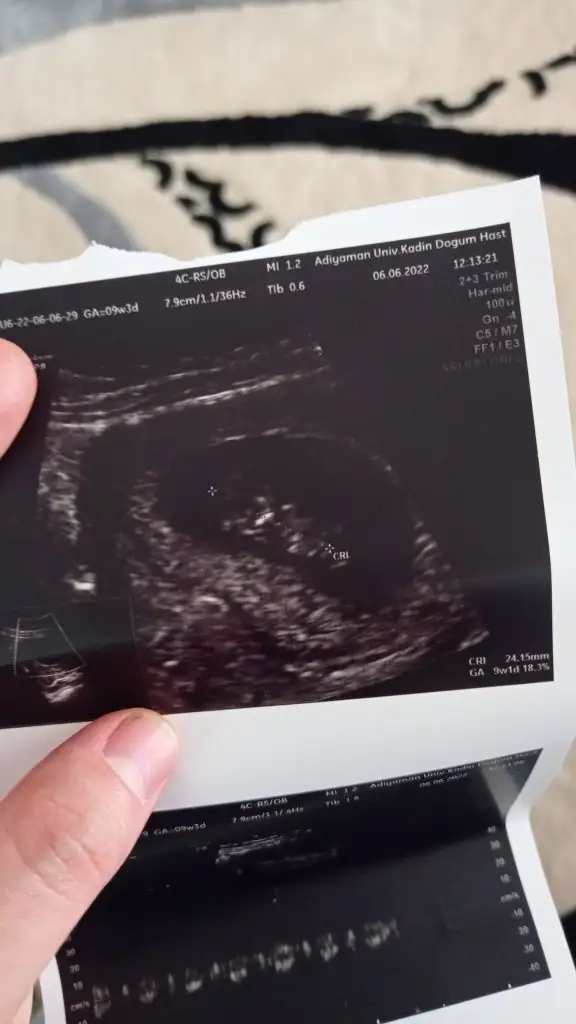

Merhaba cnm bide benimkine bakarmisin 6+3 vajinal ultrason

Eklentiler

• C109E34C-0E5F-4D6A-8E34-7EEB674397CF.webp

C109E34C-0E5F-4D6A-8E34-7EEB674397CF.webp

46,3 KB · Görüntüleme: 65